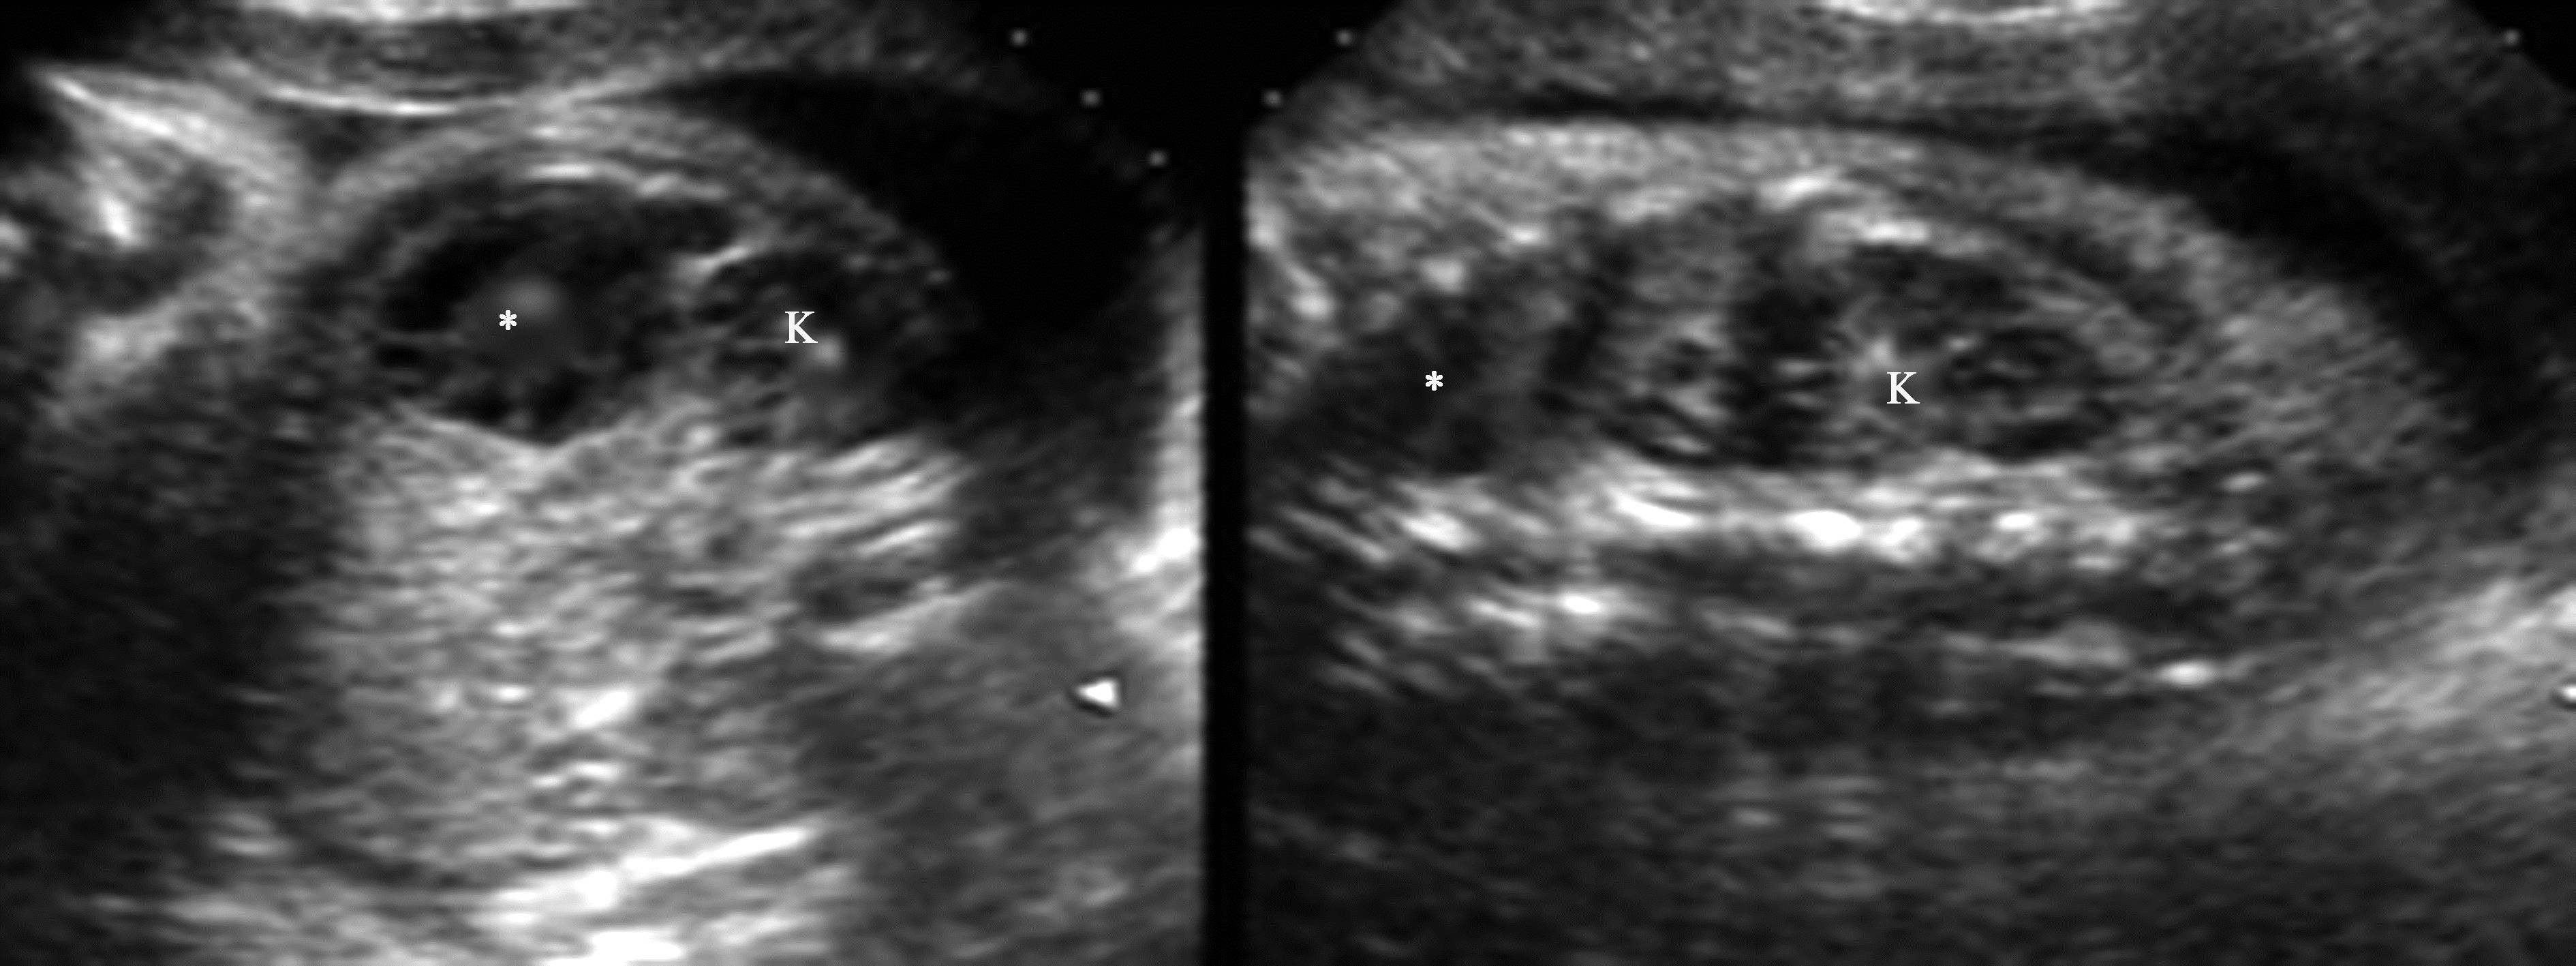

胎儿肿块在孕20周时较少发现,而到孕28周以后就相对多见了,主要原因是各器官在此时期已发育成熟。晚期妊娠是发现胎儿腹部肿瘤的主要时期,胎儿时期肾上腺及肾上极出现的肿块最多见的是神经母细胞瘤,其次是肾上腺出血、肺叶外的孤立肺、支气管源性囊肿、肾发育不全等,但此时期发现的神经母细胞瘤既可以是实质性,也可以是囊实性或囊性,因此除手术外常较难进行有效鉴别诊断。由于胎儿时期发现的神经母细胞瘤通常在生后时处于Ⅰ、Ⅱ或Ⅳ~S期,很多文献报道预后良好。胎儿肾上腺区肿块(图1)不论是良性病变或是恶性肿瘤,预后多良好,但需要生后严密观察随访。肾脏肿瘤罕见,常见的是肾中胚层瘤,位于胎儿肾内,较大,回声均匀,边界较清楚,可压迫肠管,其内彩色血流信号丰富,常伴羊水过多,生后手术成功率高,预后好。胎儿肾脏Wilms瘤很少见。

图1 孕29周胎儿左肾上腺区肿块(*)声像图